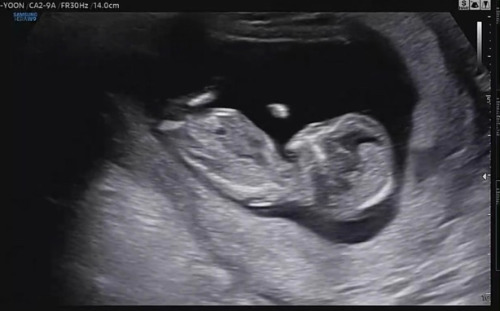

1차 기형아 검사가 있던 날. 보통 초음파 진료는 1-2분 정도로 아기가 건강한지, 기관이 잘 자라고 있는지 확인하고 끝나는데, 이번 검사는 4분 정도 걸렸다. 맘카페에서 목투명대 검사에 대해 그동안 찾아봐서 그런지 몇 mm가 나와야 정상인지, 혹시 고위험이 나왔을 때에 어떤 검사를 추가로 해야 하는지, 비용은 얼마나 드는지 대략 확인하고 나름의 마음의 준비도 했다.

지난번 보다 좀 더 커진 아기. 얼굴 이목구비가 전보다 뚜렷해졌고, 다리길이도 더 길어졌다. 척추뼈도 선명하게 보였다. 이제 소화기능도 생겨서 양수를 마신 흔적까지 확인할 수 있었다. 머리 쪽을 확인하며 뇌의 모양도 나비모양으로 잘 자라고 있다고 했다. 선생님은 "코가 엄청 높네요ㅎㅎ"라고 하셨는데, 내가 봐도 코가 높은 것 같기도 하고, 코가 또치처럼 생긴 것 같기도 했다. 남편과 내 코가 낮은 편은 아니니까 우리 띠용이 코도 낮진 않겠지? 하는 기대감이 생긴 순간이다.

그리고 목투명대 검사를 했다. 선생님은 "얘는 보지도 않아도 정상"이라고 말씀하시며 목투명대 길이를 재셨다. NT(목투명대) 길이는 0.62mm.

*NT는 보통 3-5mm 이하 일 때 저위험으로 보고, 그렇다고 하더라도 무조건 정상이라는 게 아니라 확률상 특별한 문제가 없을 확률이 높다는 것이다.